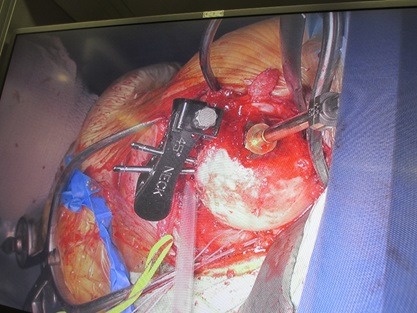

手術風景